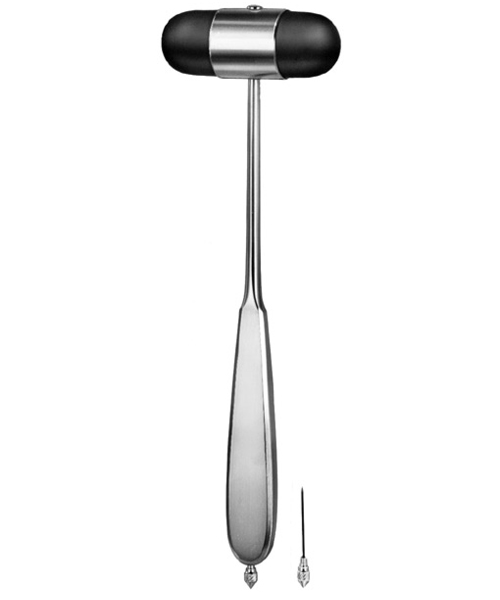

- Diagnostics, Surgical Instruments

Percussion Hammer

- Size : 14 CM - 5 1/2"

- Diagnostics, Surgical Instruments

Percussion Hammer

- Size : 16 CM - 6 1/4"

- Diagnostics, Surgical Instruments

Percussion Hammer

- Size : 18.5 CM - 7 1/4"

- Diagnostics, Surgical Instruments

Percussion Hammer

- Size : 20 CM - 8"

- Diagnostics, Surgical Instruments

Percussion Hammer

- Size : 20 CM - 8"